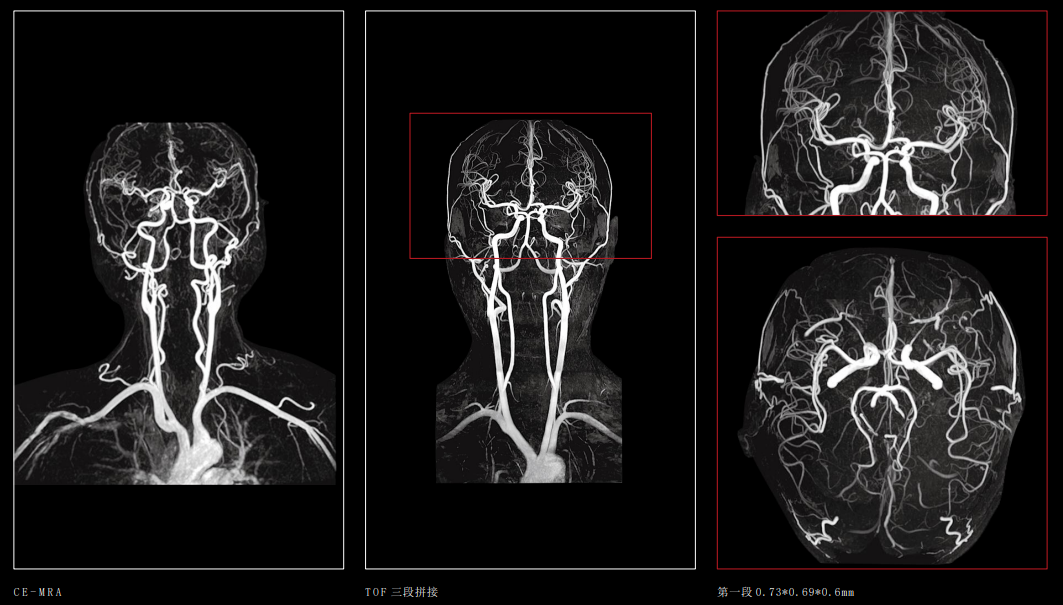

对脑梗塞、脑肿瘤、炎症、先天畸形、外伤、头颈血管壁高分辨率成像及功能成像更清晰,对病变的定位、定性诊断更准确、更及时,可发现早期病变。

联影磁共振怎么样【三级医院创建 • 技术装备提升】再添医学影像“利器”——我院引进联影uMR870  3.0T磁共振_https://www.jmylbn.com_新闻资讯_第16张

急性脑梗塞

联影磁共振怎么样【三级医院创建 • 技术装备提升】再添医学影像“利器”——我院引进联影uMR870  3.0T磁共振_https://www.jmylbn.com_新闻资讯_第17张

头颈部动脉成像

2、心血管系统:

用于血管闭塞、心脏病、心肌病、心包肿瘤、心包积液以及附壁血栓、内膜片的剥离等的诊断;纵膈内的肿物、淋巴结以及胸膜病变等,可以显示肺内团块与较大气管和血管的关系等。